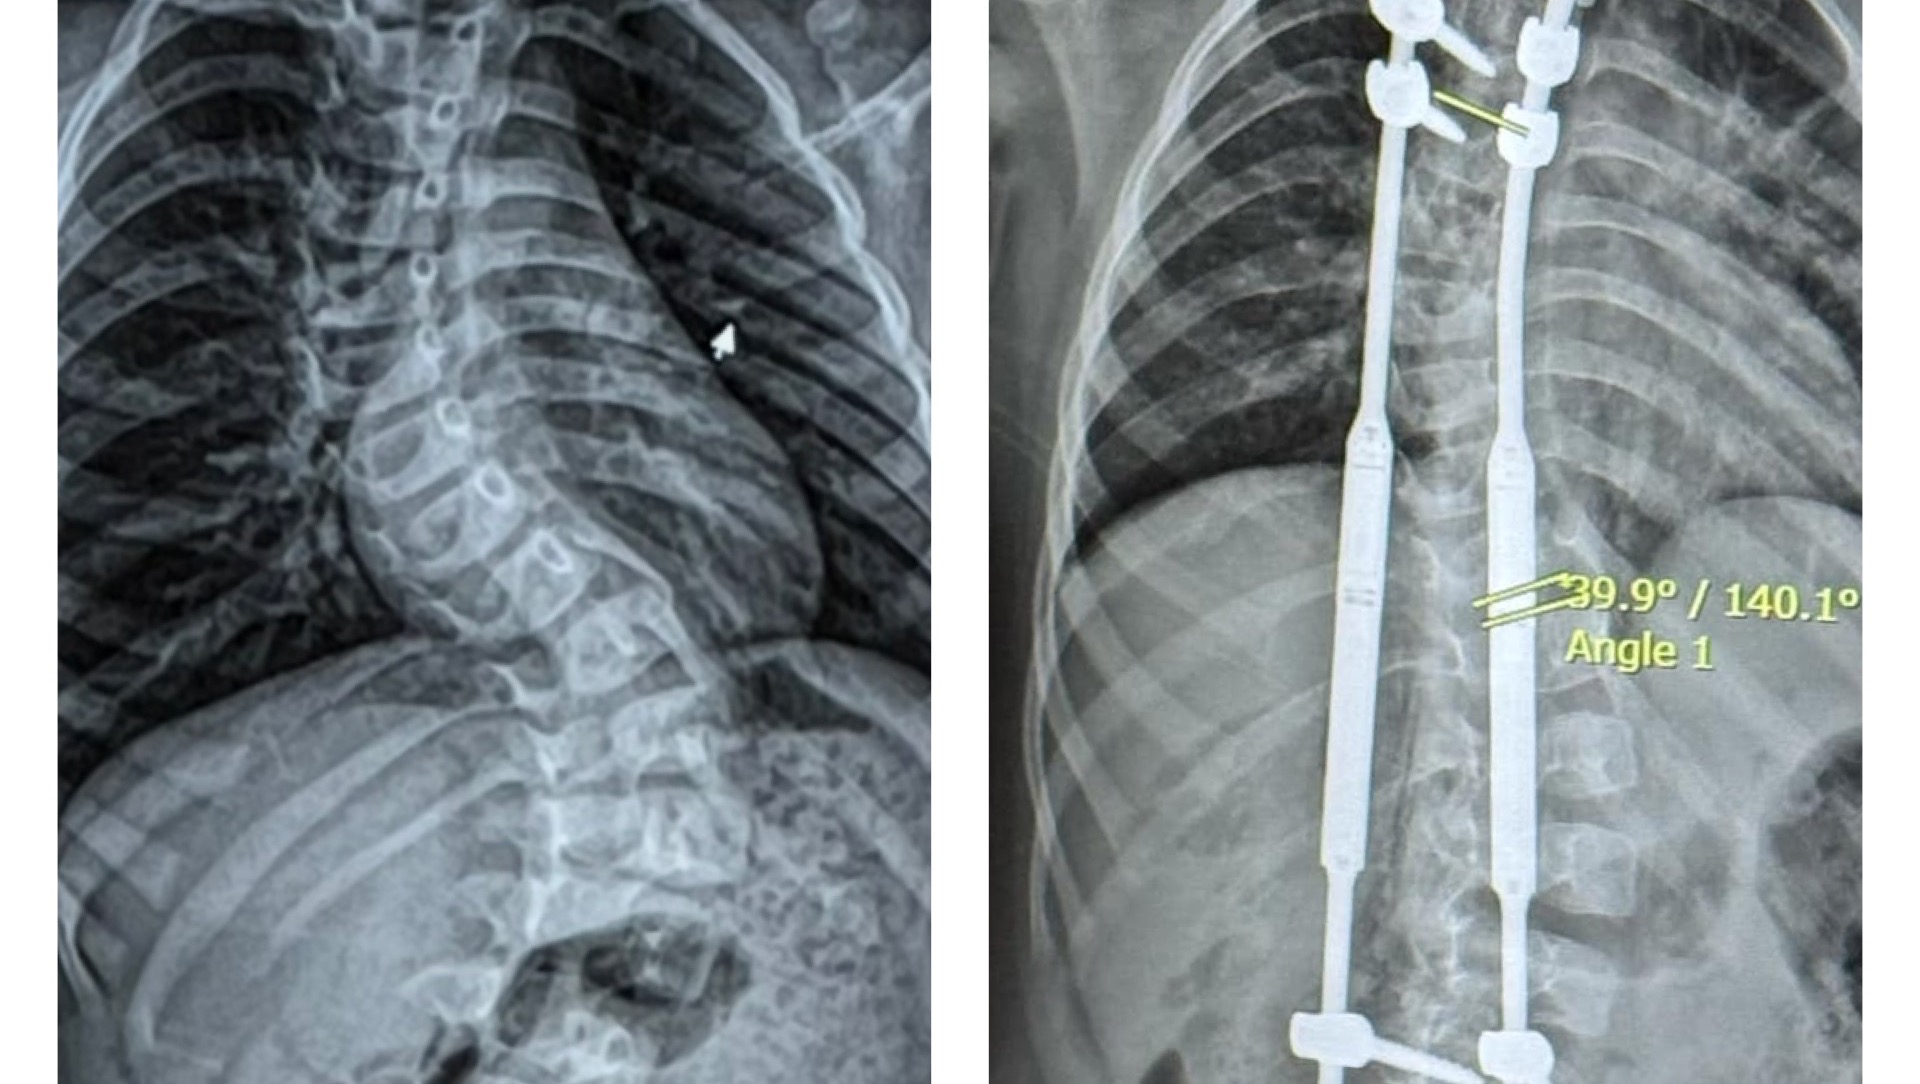

Since, Koledyn has been seen at Essentia Health in Duluth, by Dr.Kathryn Huff and several other pediatric othoropedic specialists. Koledyns spine at this time had a 67 degree curve and a 43 degree curve.

Koledyn will be having MAGEC ( MAGnetic Expansion Control System) rod surgery March 14,2025. The MAGEC system, which includes implantable rods and an external remote control, are used to brace the spine while the child is still growing to minimize the progression of scoliosis.